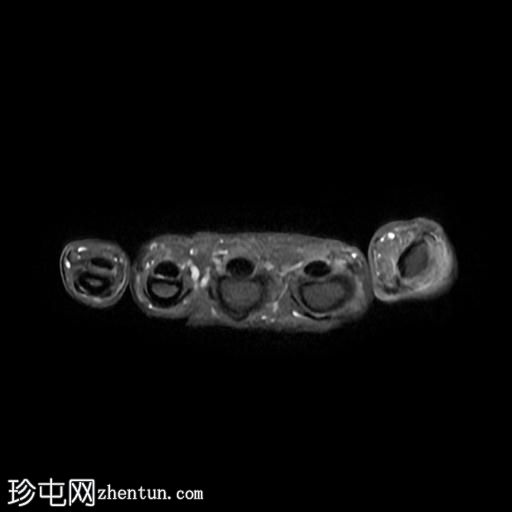

轴位

T1加权像

6.jpg